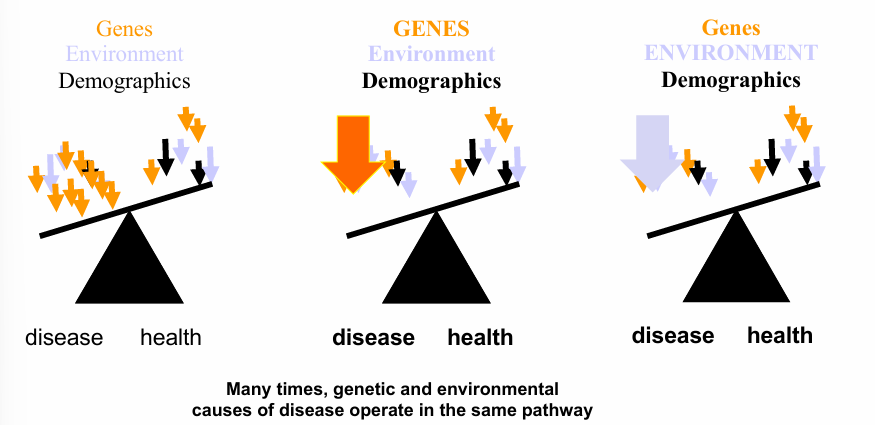

hypertension as a multifactorial disease

environmental causes of hypertension- obesity